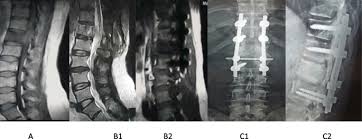

However, as with other types of cancer,. Can bone metastasis happen in the prostate cancer? Prostate cancer is one of the most common types of cancer diagnosed in men. Here are 10 more facts about prostate cancer. Find the information you need today.

The hormones that your thyroid gland produces help regulate several of your bodily functions. Prostate cancer is one of the most common types of cancer diagnosed in men. Can bone metastasis happen in the prostate cancer? The earlier the detection of prostate cancer, the better the patient's chance of survival is. Prostate cancer is a common type of cancer in men, according to the mayo clinic.